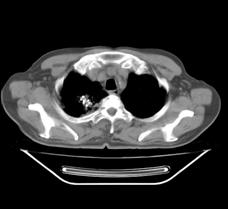

典型病例3:患者赵XX,男,76岁,住院号:493297,因咳嗽、咳痰、右侧胸痛1月余入院。于2015年5月29日胸部增强CT示:右肺上叶4.1cmx3.4cm占位。5月31日行CT引导下右肺穿刺活检术;6月1日活检病理证实:右肺上叶腺癌;6月16日行CT引导下右肺125I粒子植入治疗。7月22日患者复查胸部CT,原发病灶基本消失、粒子聚集。

术前CT片: